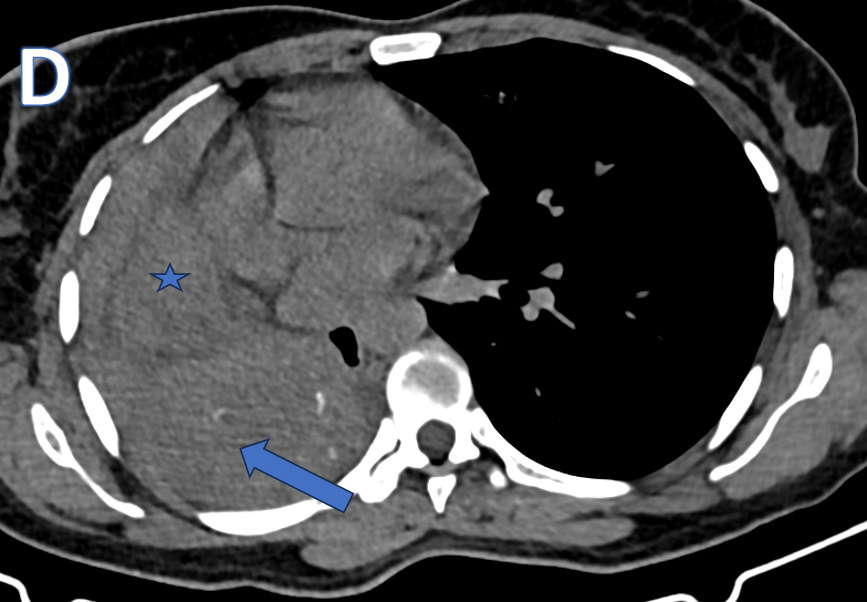

A - AP-Chest XRAY

• ARROW: Tracheal deviation to the Right.

• STAR: Opacified right hemithorax.

• Findings are consistent with Collapse of the right lung.